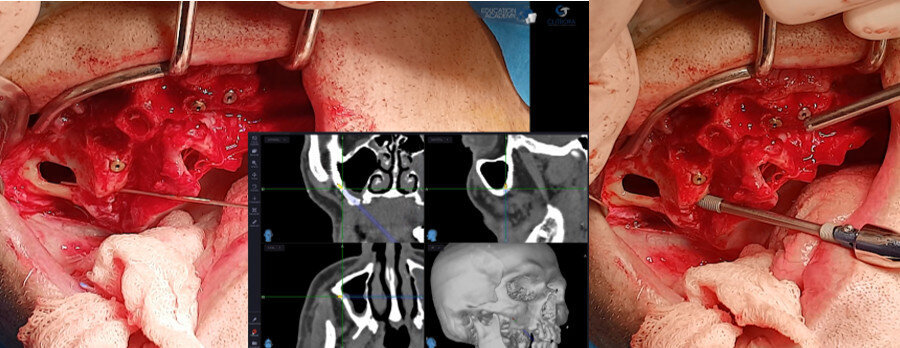

Figs. 6a & b: Placement of the first-quadrant zygomatic implant with the help of the navigation instrument.

Figs. 7a & b: Placement of the second-quadrant zygomatic implant with the help of the navigation instrument.

After elevation of a full-thickness flap with bilateral identification of the infraorbital nerves, an osteotomy was performed to create a bone window to access the interior of the maxillary sinus. The navigation instrument most suitable for this type of surgery was chosen for its flexibility, thickness and length (Fig. 5). The images displayed on the monitor are in real time intra-operatively, allowing the alteration and verification of the osteotomy in the space planes. Confirmation of existing bone availability, maintenance of the integrity of the relevant anatomical structures and placement of the zygomatic implant in the ideal position for each clinical case are ensured. Zygomatic implants are placed according to this checklist (Figs. 6a–7b). The 3D positioning of the zygomatic implants allowed excellent primary stability as well as adequate positioning for prosthetic restoration (Fig. 8).